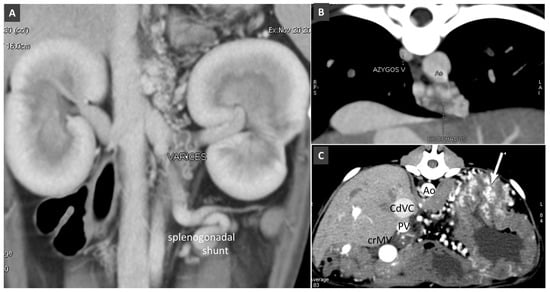

3.5. Anomalous Vascular Connections of the Portal Vein System

3.6. Low-Flow Anomalous Portal Connections

Congenital Portosystemic Shunt

3.8. Porto-Portal Collaterals or Cavernous Transformation of the Portal Vein